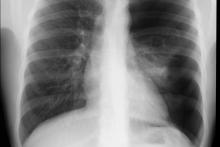

Przypadek 1: 16-latek z bólami w klatce piersiowej. Rozpoznanie: Odma opłucnowa lewostronna. Niedodma płuca lewego.